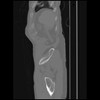

7 CUERPO,CE,Sagittal,3.000,CUERPO,Sagittal,